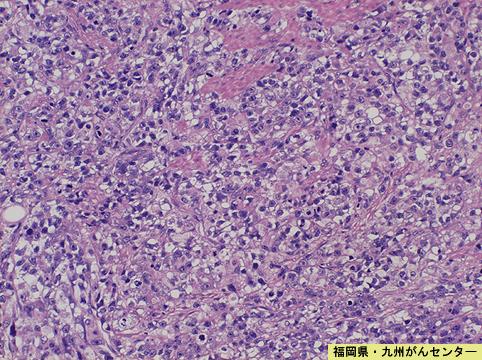

疾病(病理主体)的分类恶性上皮性肿瘤/腺癌

部位(按器官分)胃(部位)/体部

检查方法病理切片(微观)

肿瘤的肉眼分类5型(难以分类)/

肿瘤最大直径40以上

肿瘤的深度ss(a1)